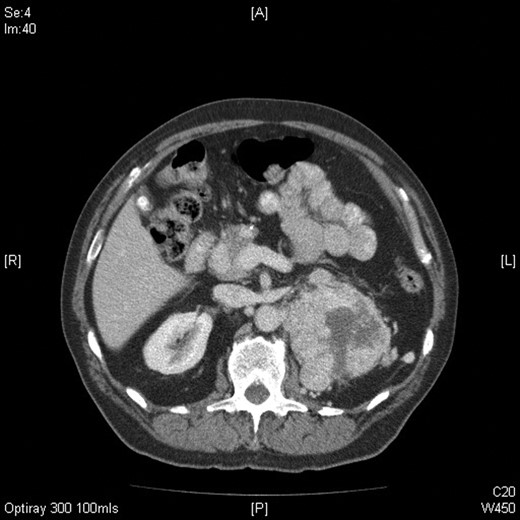

Axial CT image of the abdomen confirming the presence of a large mass arising from the superior pole of the left kidney measuring 13 (craniocaudal) × 8.5 (side to side) × 9 (AP) cm with central areas of necrosis.